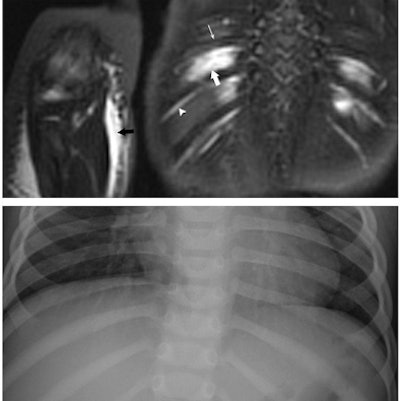

| Images are of a 17-month-old boy with suspected nonaccidental trauma. Coronal WB-STIR (top) of posterior chest wall and right elbow demonstrates edema of intercostal muscles (large arrow), but no fracture of adjacent ribs (thin arrow). Note normal hyperintense subcostal neurovascular bundle (arrowhead). There is diffuse subcutaneous edema of right antecubital fossa (black arrow) related to failed catheter placement. Corresponding RBS (bottom) corroborates absence of rib and elbow (not shown) fractures. Images courtesy of Dr. Peter Evangelista. |

Whole-body STIR also identified 43 additional soft-tissue lesions -- 34 (79%) were associated with fractures, five (12%) were iatrogenic (related to intramuscular injections), and four (9%) were deemed primary traumatic injuries. There were five additional hyperintense marrow foci that did not have any fractures on initial RBS or in follow-up, which were deemed to be traumatic bone edema.